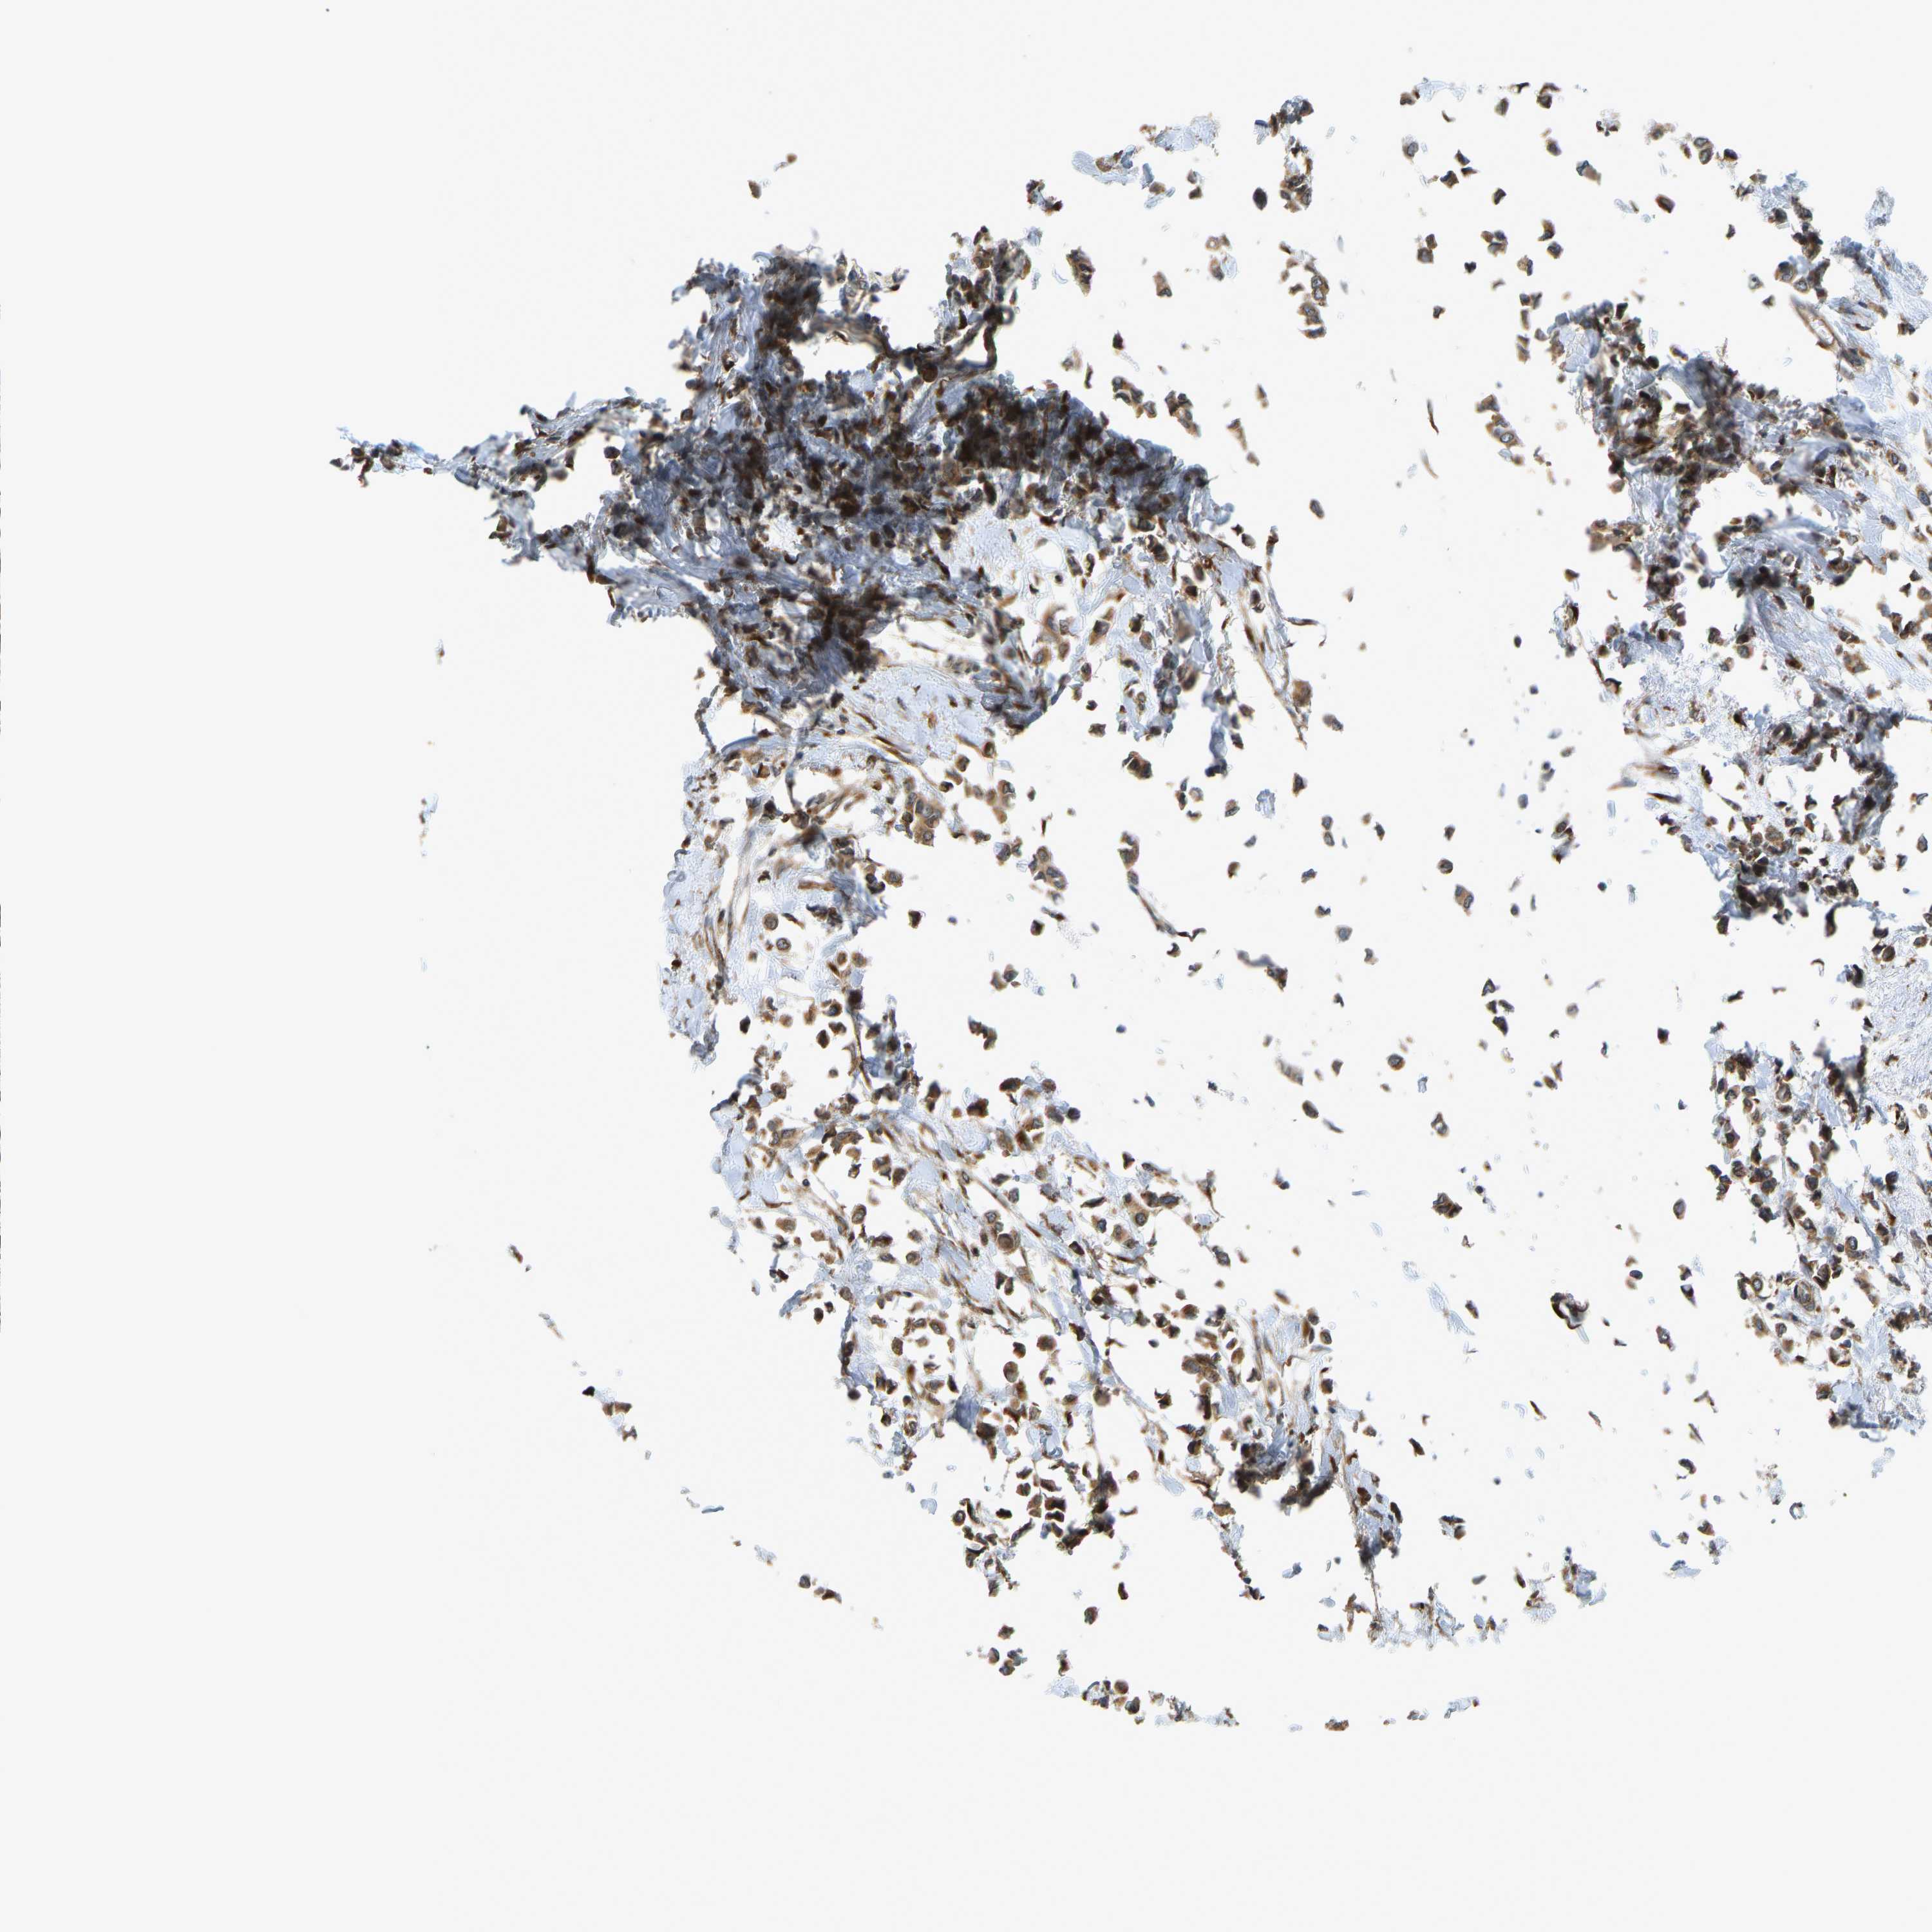

CANCER BREAST CANCER Show tissue menu

BRCA TCGA BRCA VALIDATION PROTEIN EXPRESSION

ANTIBODIES

AND

VALIDATION